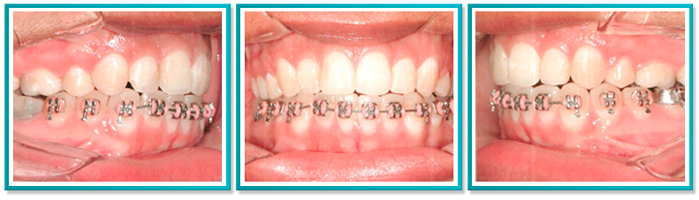

8. CORREÇÃO DE DENTES PARA FRENTE

Abaixo, fotos da correção de overjet (dentes para frente) e apinhamento (falta de espaço para acomodar todos os dentes).

A seguir, fotos da última consulta antes da remoção total do aparelho.

Caso resolvido com a extração de dois dentes superiores em 2 anos de tratamento.